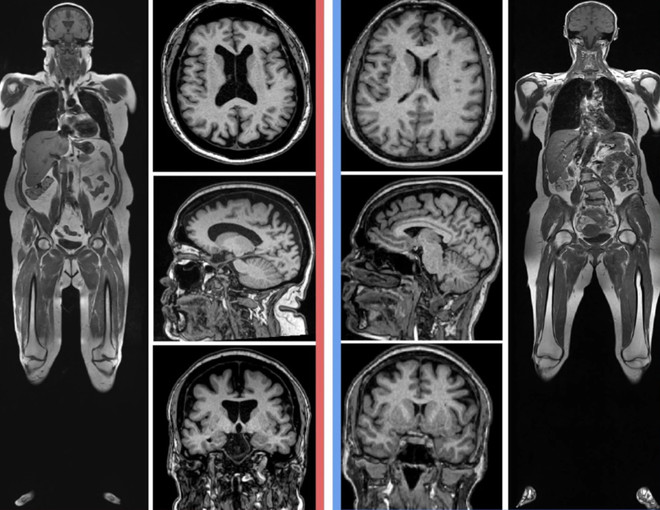

Giáo sư Raji đã phân tích ảnh chụp MRI toàn cơ thể của hai phụ nữ 61 tuổi: một người có lượng mỡ nội tạng và dưới da cao, người còn lại có lượng mỡ bình thường.

Chứng teo não xuất hiện rõ ràng ở người phụ nữ có lượng mỡ cơ thể cao hơn. Kết quả MRI não của người này cho thấy những khoảng trống rất rộng.

Vòng eo to có liên quan đến chứng mất trí nhớ khi về già? ảnh 3Chứng teo não xuất hiện rõ ràng với nhiều khoảng trống trong não ở người phụ nữ có lượng mỡ cơ thể cao hơn (bên trái). (Nguồn: Cyrus Raji)

Giáo sư Raji nói: “Chúng tôi đã tìm thấy sự khác biệt về giới tính, trong đó phụ nữ có mức độ teo não cao hơn nam giới liên quan đến việc tăng mỡ bụng.” Nhưng điều này cần nghiên cứu thêm.